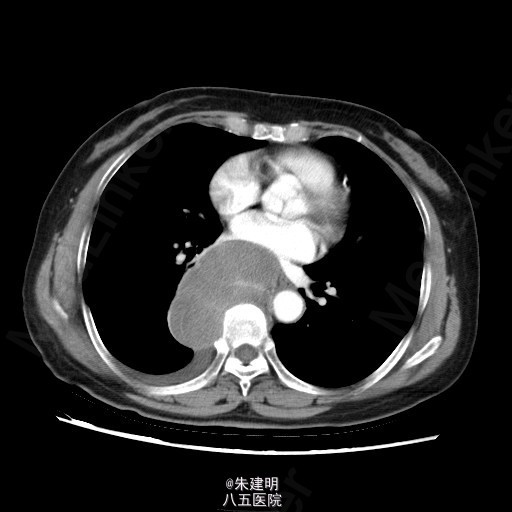

【主诉】 胸部不适1月 【现病史】 患者1月前于当地医院常规体检发现纵隔部占位,为明确诊断,遂来我院门诊就诊。门诊行CT检查(2015-05-07)示:右后下纵膈占位,梭形细胞肿瘤(神经源性等)机会大,右侧少量胸腔积液;左肺炎性小结节机会大,随访。门诊拟诊断为“右侧纵隔占位”收入我科。患者病程中,一般情况可,胃纳二便无殊。

查体: T:36.6℃ P:78次/分 R:20次/分 BP:120/80mmHg 神清,一般可,双侧锁骨上淋巴结未及肿大;胸廓无畸形,呼吸运动平稳,胸廓活动度可;两肺呼吸音清,未及明显干湿罗音。 辅助检查: 门诊行CT检查(2015-05-07)示:右后下纵膈占位,梭形细胞肿瘤(神经源性等)机会大,右侧少量胸腔积液;左肺炎性小结节机会大,随访。